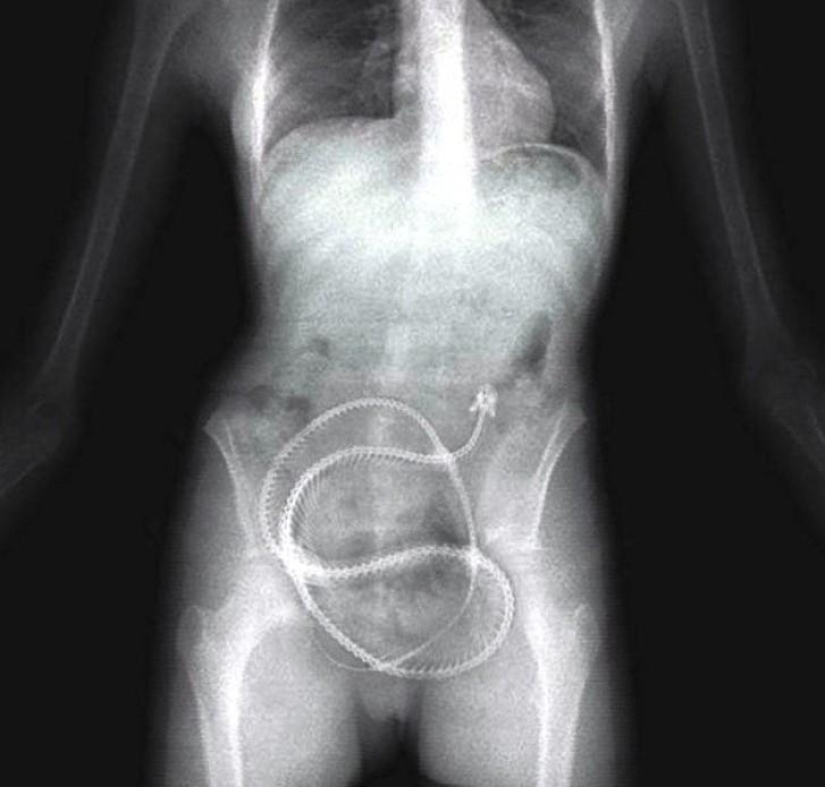

22. Pinzas quirúrgicas.